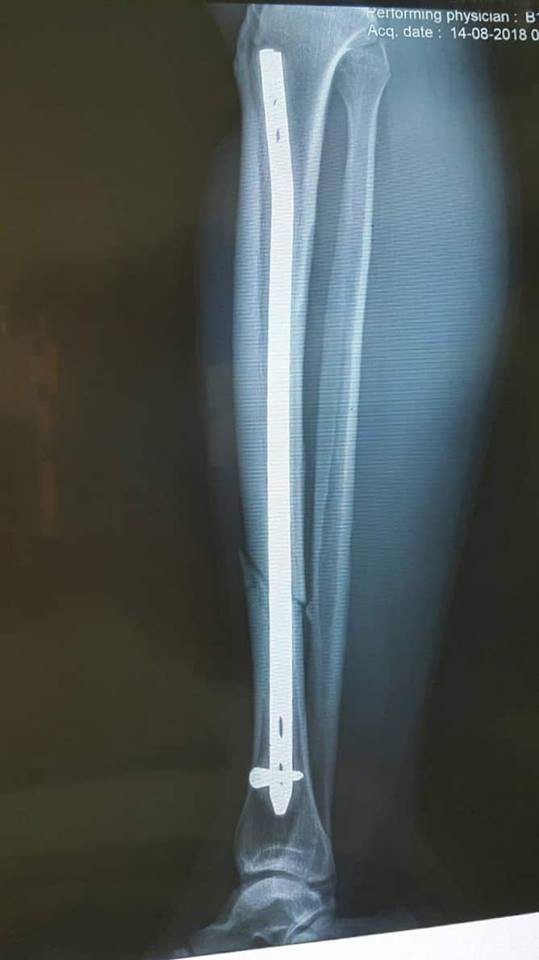

Bệnh nhân nhập viện trong tình trạng toàn thân ổn định, đau hạn chế vận động cẳng chân phải. Ngay sau khi tiếp nhận bệnh nhân, các bác sĩ đã đưa bệnh nhân đi chụp XQ chày chân phải.

Qua phim chụp, các bác sĩ xác định anh Phạm Văn Tuyền bị gãy kín 1/3 giữa xương chày phải. Sau đó, anh Tuyền được đưa đi phẫu thuật đóng đinh nội tủy xương chày phải có chốt dưới màn tăng sáng, không mở vào ổ gãy.

Hiện tại, tình trạng sức khỏe của anh Tuyền ổn định sau một ngày phẫu thuật.